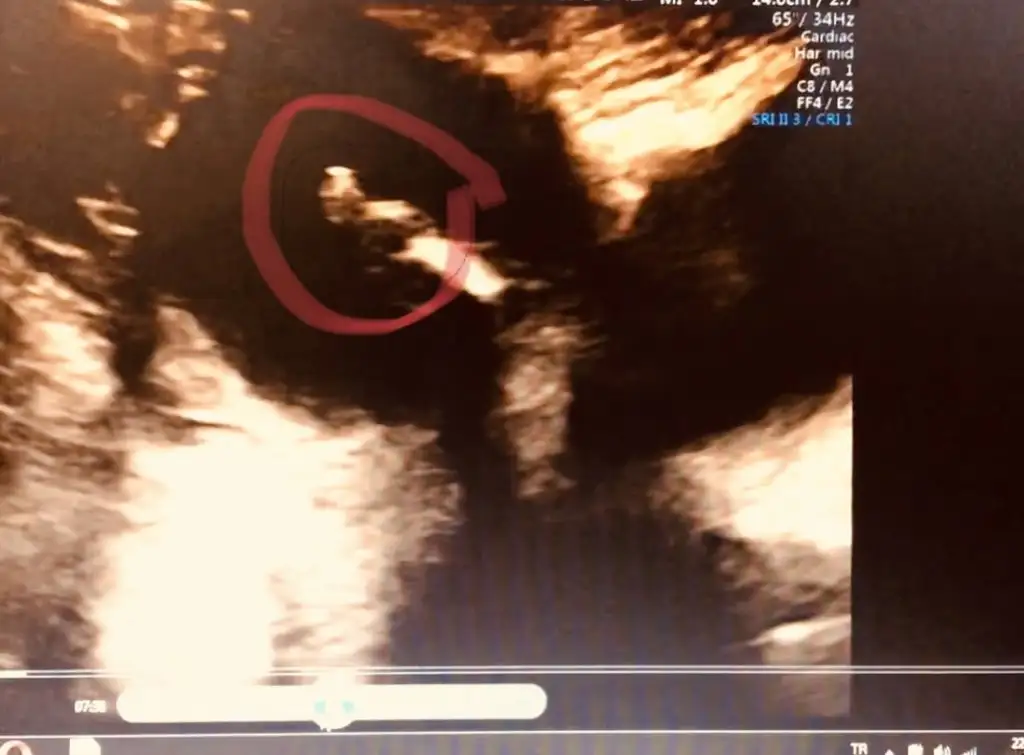

Kız gibiMerhaba hanimlar gecen hafta yazmistim nub icin 11 sonrasi daha iyi olur demistiniz bugunde kontrolden geldim cikar mi bi tahmin acaba❤

Başka usg varsa paylaşın net degilMerhaba hanımlar 11. Haftadayız bizede bir cinsiyet tahmini yaparmisiniz![]()

Erkek geliyor canım :)Kız 13+ haftadasınız

13+ haftasında nub olmaz bende kafa yapısına kız dedim saglıkla gelsin ogluşunBanada tahmin yapın kızlaaar![]()

Dr daha iyi goruyor ama bu usg ye gore KizzzMerhaba hanimlar gecen hafta yazmistim nub icin 11 sonrasi daha iyi olur demistiniz bugunde kontrolden geldim cikar mi bi tahmin acaba❤